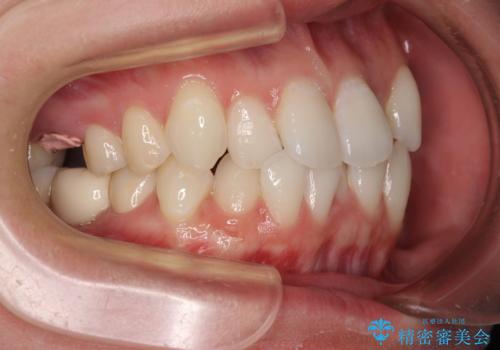

- 2、3年後にワーキングホリデーで海外に行くため、その前に歯列やむし歯をきれいにしたいとのことで来院された患者様です。

抜歯の必要な右上の奥歯は事前に抜歯をし、インビザラインにて上下歯列を整えることとしました。

矯正治療後半に奥歯の補綴治療が必要な歯にはオールセラミッククラウンを装着し、インビザラインで最終的に仕上げることとしました。